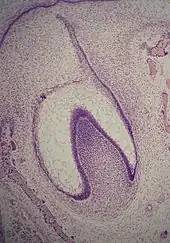

A: organe de l'émail avec la lame dentaire

B: papille dentaire

C: follicule dentaire.

La formation d'une dent commence donc par un agrégat cellulaire, le germe dentaire[2], dérivant de l'ectoderme issu du premier arc branchial de la crête neurale[1],[3],[4]. Ce tissu d'origine ectoblastique va se transformer en un tissu mésenchymateux appelé ectomésenchyme ou mésenchyme ectodermique. Le germe dentaire est divisé en trois parties : le bourgeon dentaire (ou organe de l'émail ou encore organe adamantin), issu de l'ectoderme, la papille dentaire et le follicule dentaire, issus du mésenchyme.

Le début de l'agencement des cellules dans le bourgeon dentaire se produit au stade de la cupule. Dans le mésenchyme, tissu conjonctif, un petit groupe de cellules cesse de sécréter le substrat extracellulaire qui les entoure, ce qui va se traduire par un rapprochement des cellules entre elles et former la papille dentaire. À ce stade, le bourgeon dentaire se développe autour de cet agrégat, prenant la forme d'une cupule et devient l'organe de l'émail. Des cellules du mésenchyme vont s'agglomérer autour de l'organe de l'émail et de la papille dentaire pour former le follicule dentaire. La papille dentaire va alors produire la dentine et la pulpe, l'organe de l'émail va produire de l'émail et le follicule dentaire produire le parodonte, les structures de soutien de la dent[1].